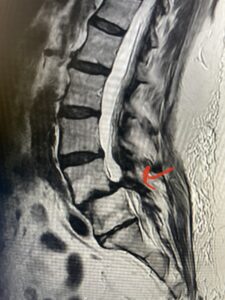

This 73 year-old female had a long history of low back pain and left thigh pain and heaviness of her legs when she ambulated or did activities. She failed all means of conservative treatment including epidurals and PT. On exam she had mild weakness of her left quad but otherwise was intact. Lumbar MRI (Fig 1) revealed significant L4-5 lumbar stenosis and a grade 1-2 spondylolisthesis. Her main pathology was severe, thickened “knobs” of ligamentum forming at the posterior margin of the superior facet processes of L5 and lamina (Fig 2). The patient underwent a decompressive laminectomy of L4 as well as removal of the inferior processes of L5 to widely decompress bilaterally the L4 and L5 nerve roots. Intraoperatively, the descending L5 nerve roots were compressed severely by this severe thickened ligamentum in the subarticular recess. Because of the significant spondylolisthesis we augmented her decompression with fusion. She underwent an L4-5 posterolateral fusion with segmental instrumentation (Fig 3)). Postoperatively she had an uneventful course with relief of her leg pain.

Fig 1: Sagittal T2-weighted lumbar MRI demonstrating grade 1-2 spondylolisthesis L4-5 with severe stenosis (red arrow)